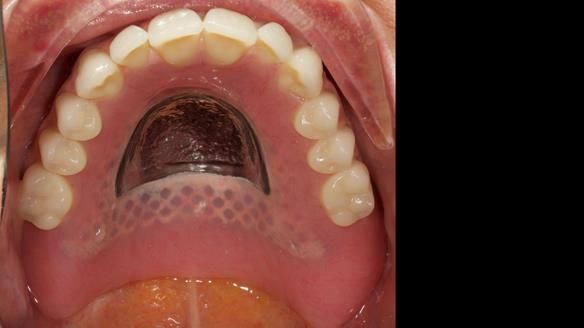

This newsletter describes in step by step detail the provision of a lower implant supported metal based complete denture with three dental implants positioned in the anterior mandible. The upper arch was restored with a metal based complete upper denture.

Mary had 3 dental implants placed in the anterior mandible 10 years previously with new complete dentures. These were successful for a time. The dentures were replaced a few years later. Mary was never pleased with the new lower denture as they did not fit the implants properly. This patient was referred to me from Ireland, to my practice in Garstang, England.

- Locator attachments not engaging the housings in the lower denture.

- Suboptimally shaped dentures with poor tissue fit resulting in rocking of the dentures.

I provided new metal based complete dentures. The clinical situation and treatment process is shown in detail below with photographs. I provided the clinical work and Rowan Garstang provided the technical work. The dentures took 5 visits to make - with the patient travelling by plane from Ireland to Manchester. The patient had one review after the dentures were fitting.